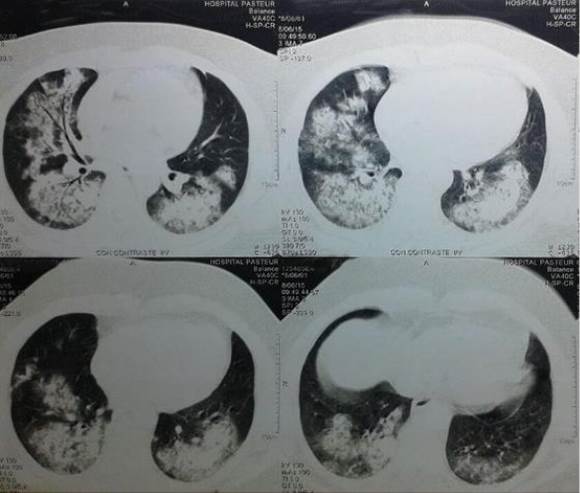

Radiografía de tórax: infiltrado intersticial bilateral y difuso que compromete los 4 cuadrantes. Angio-TAC tórax: imágenes en vidrio deslustrado con ocupación alveolar bilateral y difusa, sin foco de condensación. Sin lesiones vasculares pulmonares (Figura 3).

Con planteo de vasculitis sistémica con afectación pulmonar se inician bolos de metil-prednisolona 1 gr iv/día por 3 días y bolos de Ciclofosfamida 1 gr/mes durante 6 meses con excelente evolución clínico, paraclínica e imagenológica (Figura 4).

Figura 4: Caso clínico 2: TAC tórax control post bolo de Ciclofosfamida con franca mejoría imagenológica